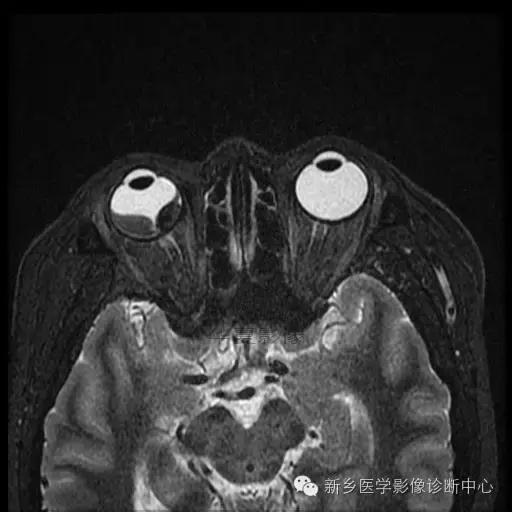

脉络膜黑色素瘤

脉络膜黑色素瘤是由恶性黑色素瘤细胞组成的神经外胚叶性肿瘤, 其组织发生于脉络膜基质内的黑色素细 胞, 国内发病率仅次于发生在儿童的视网膜母细胞瘤, 居眼内肿瘤的第二位, 少数病例可向眼眶蔓延, 晚期向肝脏转移,老年人居多。

影像:

(1)CT:早期眼环局限性增厚;突入玻璃体腔后, 表现 为 密度均匀、边界较清楚的等密度或略高密度半球形或球形肿块;肿瘤较大时,外形不规则, 可占据整个玻璃体腔。可侵犯巩膜外、视神经,可继发视网膜脱离。

(2)MRI:肿瘤边界光 整, 多呈蘑菇型,T1WI呈高或极高信号,T2WI呈低信号。增强扫描肿瘤强化而视网膜及脉络膜下积液及眶内脂肪不强化。